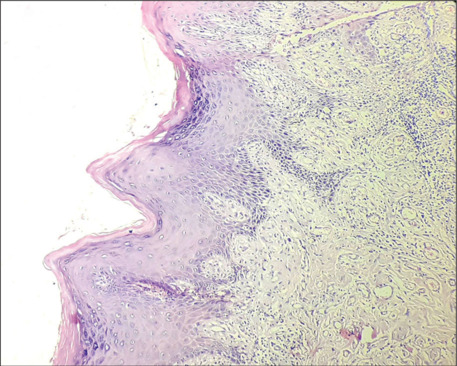

口腔白斑是一种常见的口腔潜在恶性疾病,如果不及时治疗,可能会发展为口腔鳞状细胞癌。虽然舌和颊粘膜是最常见的受累部位,但累及腭龈是相对罕见的。它通常与高复发率和更高的恶性转化倾向有关。手术切除病变被认为是金标准的治疗策略。本病例报告描述一例口腔白斑累及腭龈在一个71岁的男性没有有害的口腔习惯。病变采用手术切除治疗,缺损采用对侧腭龈游离龈移植物修复。虽然术后2年未见复发,但建议患者定期监测。

Oral leukoplakia is a frequently encountered oral potentially malignant disorder that, if left untreated, could progress to oral squamous cell carcinoma. Though the tongue and buccal mucosa are the most common sites to be affected, the involvement of palatal gingiva is relatively rare. It is usually associated with high recurrence rates and a higher tendency to undergo malignant transformation. Surgical excision of the lesion is considered the gold-standard treatment strategy. This case report describes a case of oral leukoplakia involving the palatal gingiva in a 71-year-old male having no deleterious oral habits. The lesion was treated using surgical excision, and the defect was repaired using a free gingival graft from the opposite palatal gingiva. Although no recurrence was noted till 2 years following surgery, the patient was advised to undergo regular monitoring.